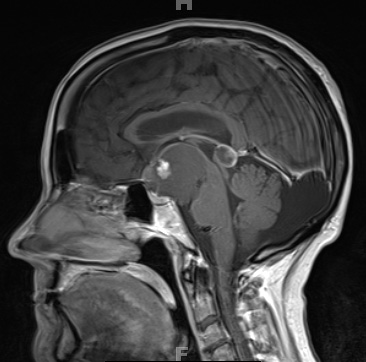

The T1-weighted hypointense suprasellar 5.3 x 4.6 x 4.0 cm mass has a 1.1 x 1.0 x 1.2 cm anterior mural nodule which enhances with contrast. The mass is hypertense on a T2-weighted scan (2A6). The mass extends into the prepontine cistern and the interpeduncular cistern as well as into the right Sylvian fissure, and displaces the optic chiasm superiorly as well as the basilar artery laterally. It is seen encasing the bilateral optic nerves, the right A1 segment and the proximal right middle cerebral artery.